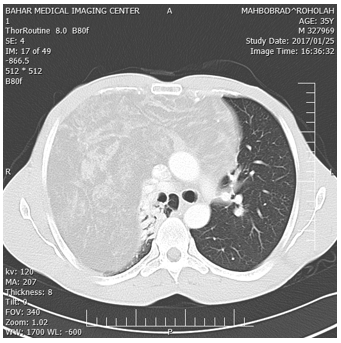

The patient is 30 year old man who has been struggling with progressive chest pain and productive cough, dyspnea and right side neck swelling for the last two years. The symptom has been increased by the last two month .In physical examination in right side of neck a soft tissue mass was palpable. The history of past medical, he had a sever car accident in two year ago and chest tube insetion in right hemithorax because of hemothorax and laparatomy. Breath sound in right hemithorax was absent. The heart biting was palpable in in five intercostal space in middle axilla line, others was normal. CXR, show completeopassification of right hemithrax. Pulmonary function tests showed a decrease in forced vital capacity (47% predicted) and forced expiratory volume (42% predicted) with a total lung capacity of only 72%. These findings were interpreted as being consistent with mixed obstructive and restrictive lung disease. During his diagnostic evaluation, a computed tomographic scan was performed, CT scan show a huge mass of anterior mediastinum and right hemithorax with extension to left hemithorax and neck,the mass was collapsed totally the right lung and shift mediastinum to the left side and compressed the heart. The Radiologist’s report was liposarcoma or teratoma (Figure 1-3).

Figure 1: Showing CT scan of chest showing anterior mediastinal fatty tissue mass with strands and islands of soft tissue with extension to occupying total right hemithorax and to left hemithorax.

Haematological and serological investigations, including tumor markers (alphafetoprotein, lactate dehydrogenase, beta human chorionic gonadotrophin, and alkaline phosphatase) were normal and not contributory to the diagnosis. With these radiologist report, the patient underwent to US-needle biopsy identified atypical cell and suspicious to liposarcoma. On completion of the preoperative evaluation, a right extensive posterolateral thoracotomy was performed via the fifth intercostal space. a large, encapsulated, vaguely lobulated mass was found within the anterior mediastinum. The mass arose in the anterior mediastinal fat, increasing in size as it extended above to the right side of neck and to the superior vena cava to the right inferior pulmonary vein, and extended to left hemithorax, compress the heart, diaphragm and shifted the mediastinum to the left, The mass occupied approximately 90% of right and 30% of left pleural cavity, resulted in marked compression and totally collapsed of right lung and partially collapse of left upper lobe (Figure1-4).